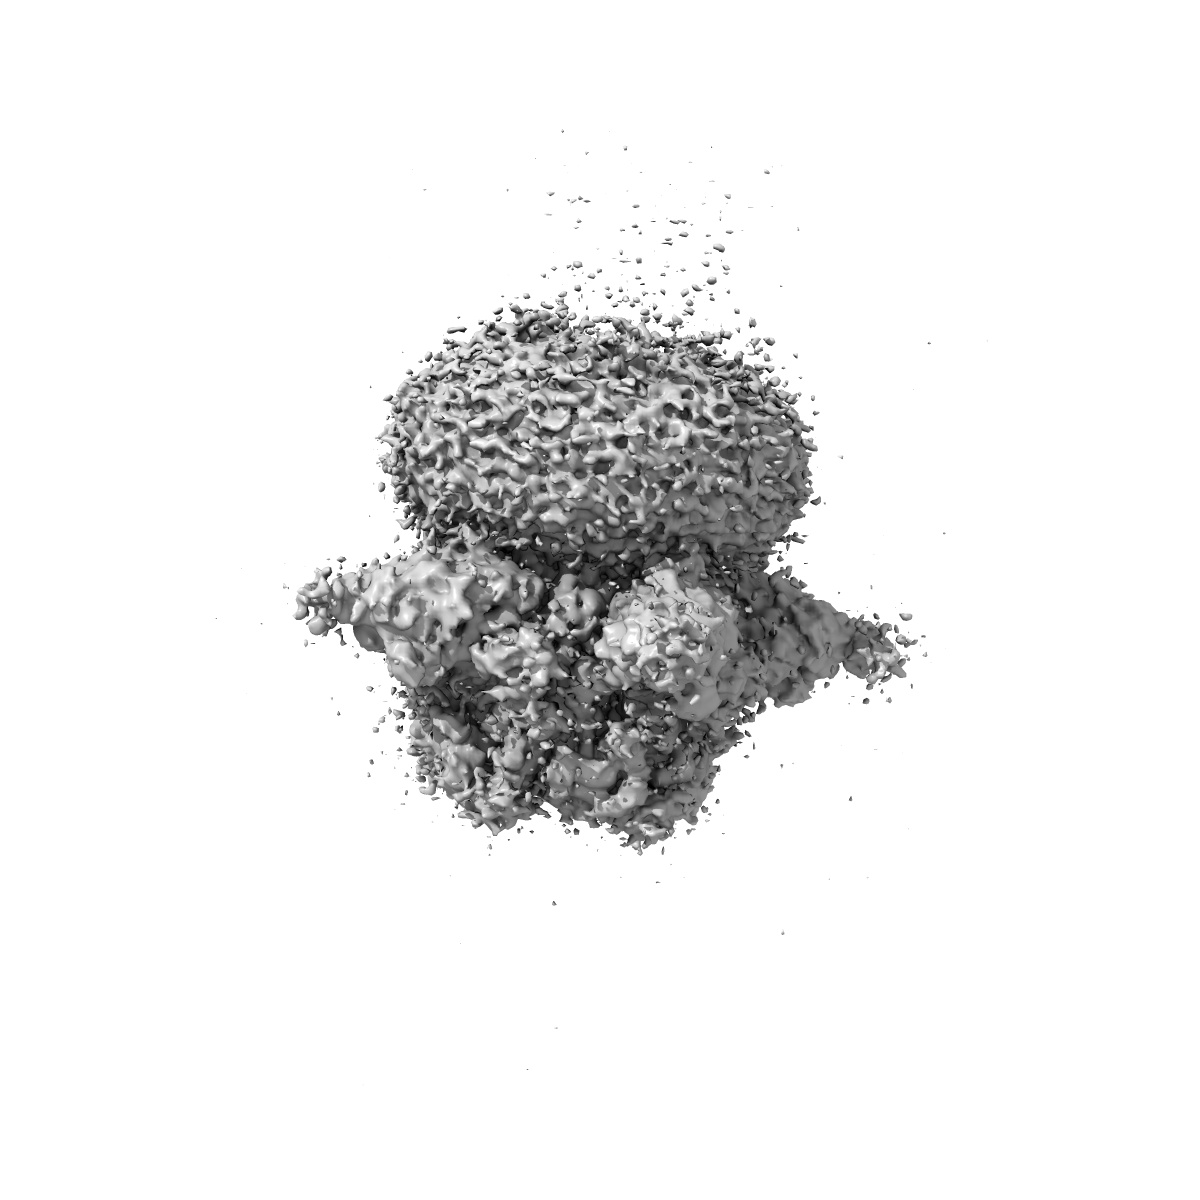

Cryo-EM structure of human full-length beta3delta GABA(A)R in complex with histamine and nanobody Nb25

Single-particle3.1 Å

Sample: Human full-length beta3delta GABA(A)R in complex with histamine and nanobody Nb25

Fitted models: 7qn8